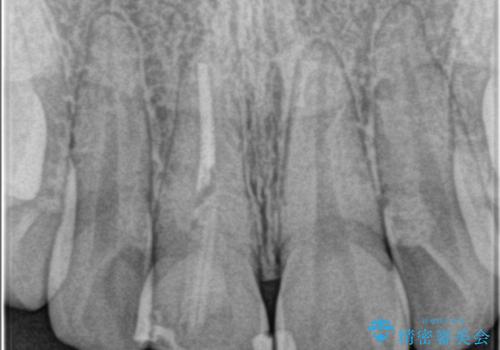

- 前歯が欠けたとの事で来院。

セラミックを希望されたので根管治療からやり直しました。

- ジルコニアクラウンスタンダード・仮歯 13.2万円 精密根管治療(リトリート)・ファイバーコア 12.1万円費用は治療当時の料金となります